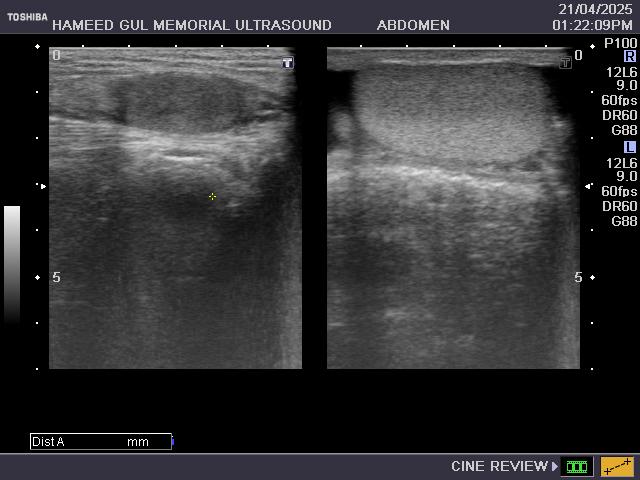

Detailed imaging of abdominal organs for diagnostic evaluation and assessment.

Liver and Gallbladder

Pancreas and Spleen

Kidney and Bladder

prostate, retroperitoneal

sub-phrenic, sub-hepatic

pleural spaces.